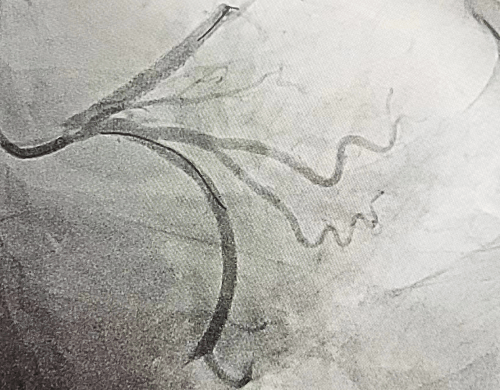

冠脈手術(shù)后

51歲的郭女士,因反復(fù)胸痛3天,加重2小時(shí)入院,入院后胸痛癥狀反復(fù)發(fā)作,檢查心電圖提示前壁導(dǎo)聯(lián)ST段明顯壓低,在此危急時(shí)刻心九科值班醫(yī)生陶醫(yī)生立即啟動(dòng)導(dǎo)管室,心九科介入團(tuán)隊(duì)行冠脈造影提示患者前降支近段99%狹窄,患者病情危在旦夕,遂立即行支架植入術(shù)解除冠脈狹窄,患者生命得以及時(shí)救治。